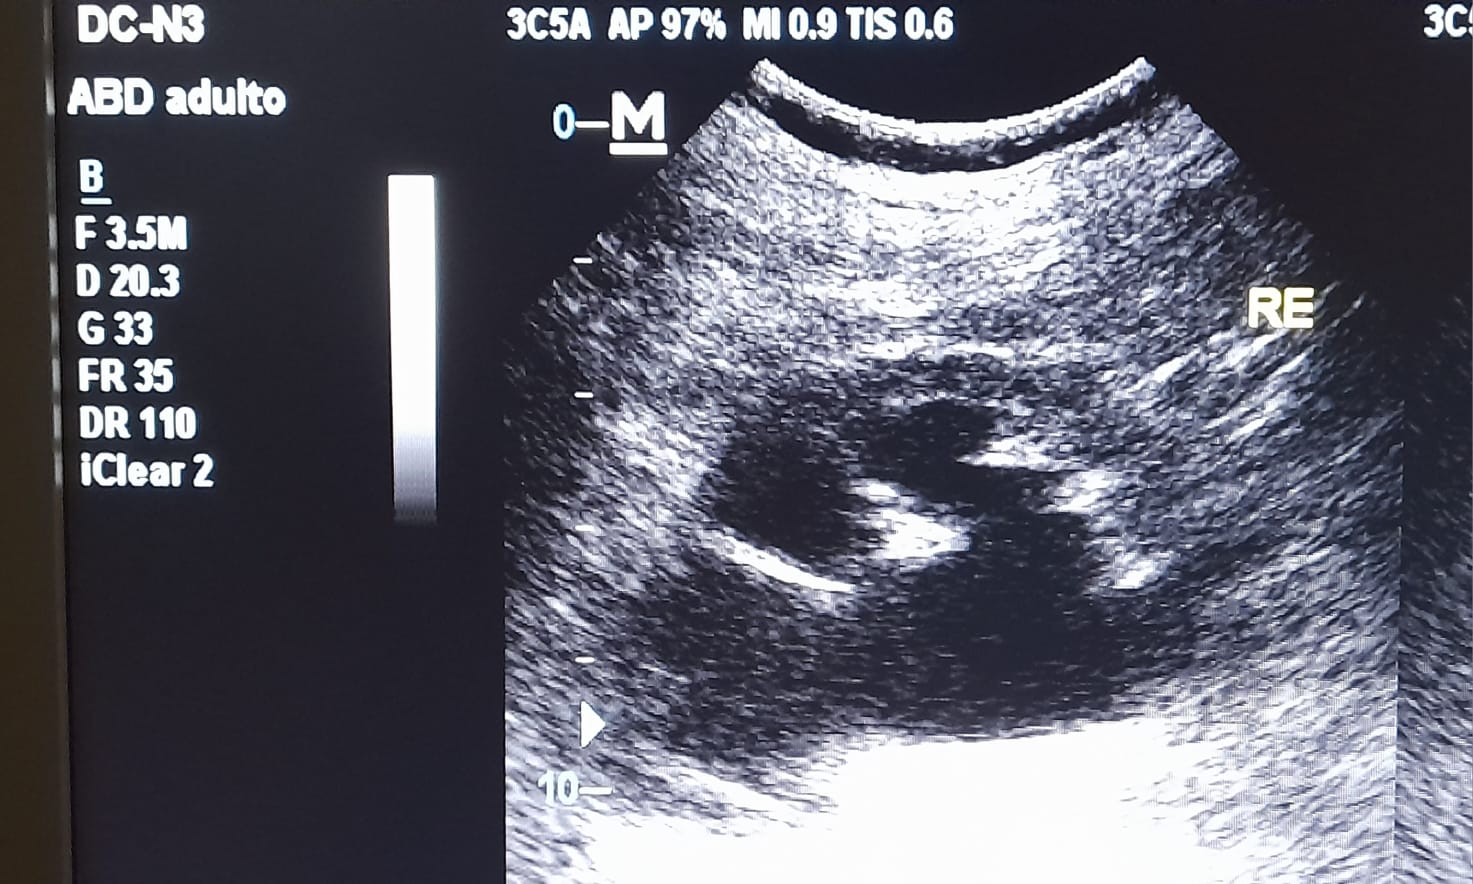

En la ecografía realizada en el ambulatorio observamos una hidronefrosis renal izquierda con líquido libre peritoneal y derivamos a urgencias de urología para estudio y manejo.

Se confirma, mediante TC abdominal, ectasia ureteropielicalicilar izquierda y posibles M1 óseas.